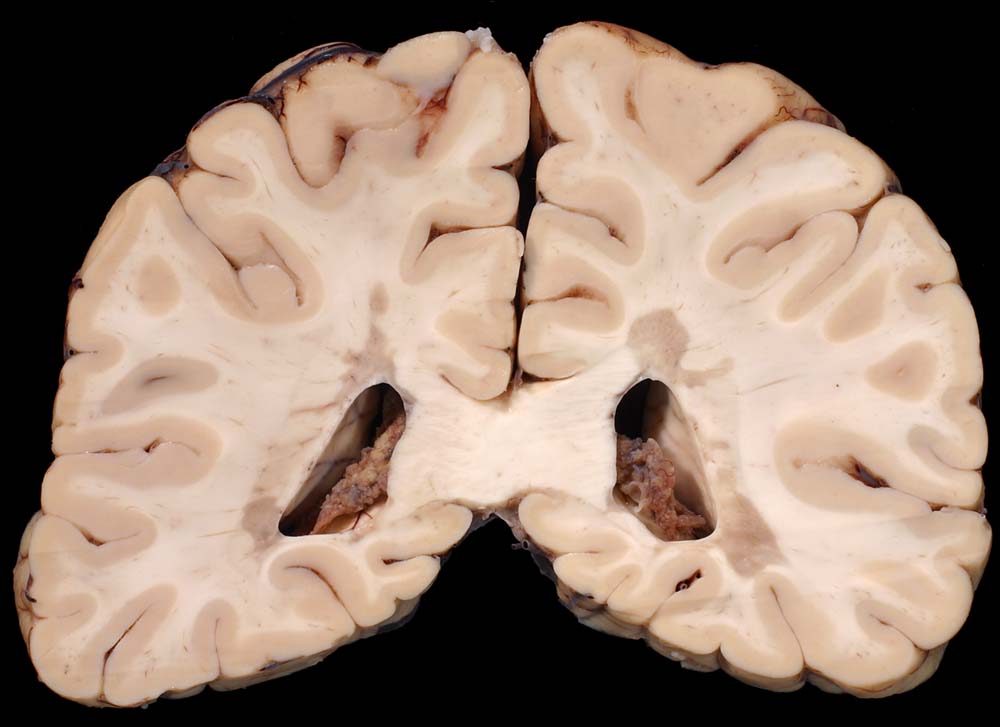

Periventrikulär betonte Entmarkungsherde bei multipler Sklerose

Periventrikuläre irregulär begrenzte Grauverfärbung des Marklagers.

Multiple Sklerose (Erstdiagnose vor 30 Jahren) mit spastischer Paraparese und neurogener Blasenmotorikstörung.